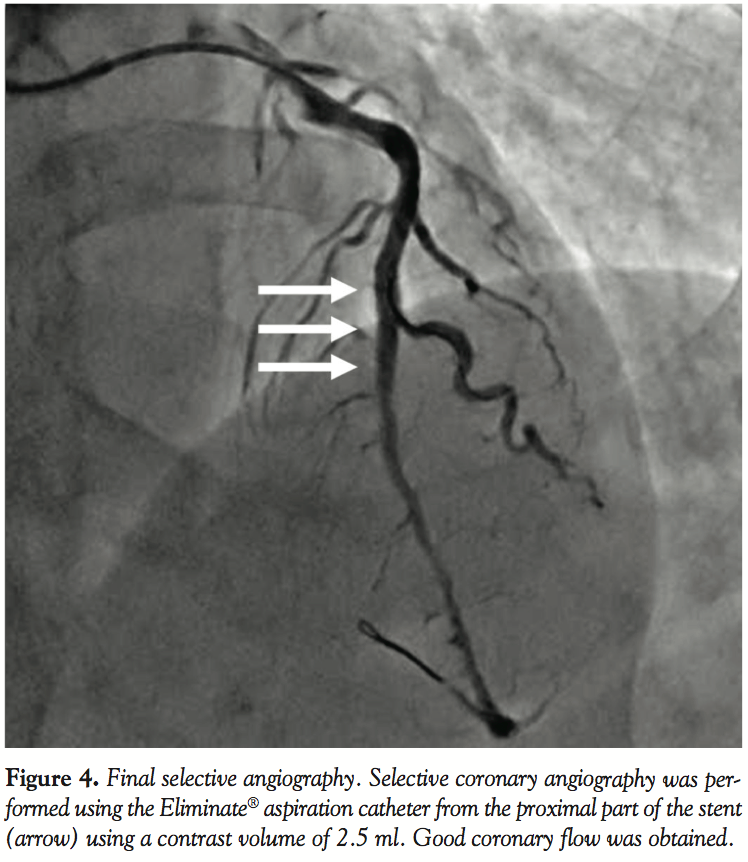

Revascularization was considered appropriate. The patient was hospitalized and PCI was performed the following day after hydration. Angiography by guide catheter was not performed. By referring to the diagnostic angiography, a Runthrough® guidewire (Terumo Medical, Somerset, New Jersey) was advanced into the diagonal artery and bifurcated immediately before the lesion. Following this step, by an Eliminate® aspiration catheter (Terumo Europe, Leuven, Belgium), selective coronary angiography was performed from the proximal part of the lesion using a contrast volume of 2.5 ml (Figure 2). Subsequently, a second Runthrough® guidewire was advanced through the lesion in the LAD using a Finecross® microcatheter (Terumo Medical). Passage of the guidewire through the true lumen could be confirmed via the sensation conveyed to the fingertips, as well as by the observation that the wire easily passed through the side branch distal to the lesion. The lesion was dilated using a 2.25 × 10 mm Ryujin® balloon catheter (Terumo Europe), and then, intravascular ultrasonography (IVUS) was performed to mark the optimal location (Figure 3). After a 3.0 × 18 mm Xience V stent (Abbott, Abbott Park, Illinois) was placed, we confirmed by IVUS that the artery was free from dissection and hematoma. After re-crossing to the diagonal artery and LAD using the Runthrough® guidewires (Terumo Medical), we performed simultaneous dilation with a 2.25 × 10 mm Ryujin® (Terumo Europe) and a 3.5 × 10 mm bpi® balloon catheter (Kaneka, Osaka, Japan). IVUS confirmed satisfactory dilatation of the stent, no malapposition, no dissection or hematoma at both edges, and no damage of the left main trunk caused by the guide catheter. Finally, selective coronary angiography was performed using the Eliminate® aspiration catheter (Terumo Medical) with a contrast volume of 2.5 ml, and satisfactory result was confirmed (Figure 4). The total amount of contrast medium during the procedure was 5 ml.

In the present case, several measures were taken to minimize the contrast volume. Preprocedure coronary angiography was not performed and selective coronary angiograms using an aspiration catheter and IVUS images were completely utilized. An aspiration catheter, which does not require the removal of the guidewire before the selective angiogram, offers sufficient luminal space to obtain satisfactory angiograms and may be the optimal device for the present purpose. We could obtain satisfactory images to assess the lesion using an aspiration catheter with a contrast volume as small as 2.5 ml without strong resistance. PCI using a smaller contrast volume could be performed safely taking these measures.